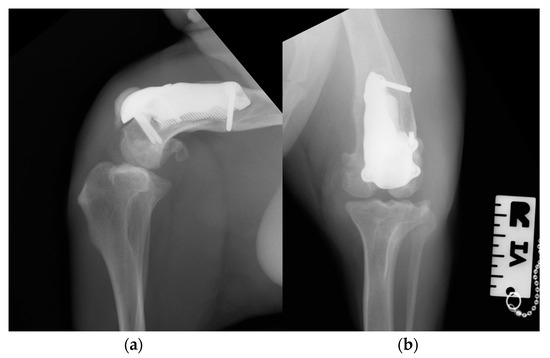

Figure 11. Three-month postoperative medio-lateral (a) and caudo-cranial (b) radiographs of the stifle joint showing the absence of implant-associated complications, such as implant loosening and migration, a thickening of the patellar ligament and mild osteoarthritic changes in the distal pole of the patella compared to postoperative radiographs.

At the 3-month postoperative follow-up, the orthopedic, radiographic and tomographic examination were repeated. The patient showed a grade II right hind limb lameness (on a scale from 0 to IV) [19] (Video S3b). On stifle joint palpation and manipulation, crepitus persisted. The arthralgia and capsular ectasia decreased compared to the postoperative follow-up, and mild pain was elicited upon palpation of the patellar ligament. The estimated angle of extension and flexion of the right stifle was 150–90°, respectively. The radiographic and tomographic evaluations revealed the absence of implant-associated complications, such as implant loosening and migration, a thickening of the patellar ligament, signs of suspicious desmitis and mild osteoarthritic progression at the distal pole of the patella (Figure 11).